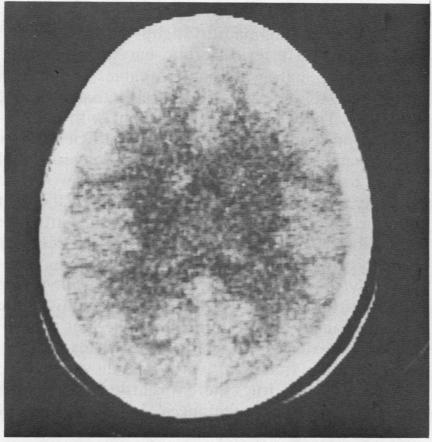

A 35 year old woman presented with headache and fever. Computed brain tomography showed diffuse low attenuation in the cerebral white matter. Several months later, serological tests for systemic lupus erythematosus (SLE) became positive. In spite of immunosuppressive therapy she relapsed after six months of treatment, presenting with abdominal symptoms and signs. On this occasion an abdominal CT scan showed distended and oedematous loops of bowel attributed to an underlying vasculitis. This case illustrates novel CT scan appearances in two systems involved in SLE.

一名35岁女性出现头痛和发热症状。脑部计算机断层扫描显示脑白质弥漫性低密度影。几个月后,系统性红斑狼疮(SLE)的血清学检查呈阳性。尽管进行了免疫抑制治疗,但治疗6个月后她仍复发,出现腹部症状和体征。此次腹部CT扫描显示肠管扩张且水肿,归因于潜在的血管炎。该病例说明了SLE累及的两个系统中CT扫描出现的新表现。